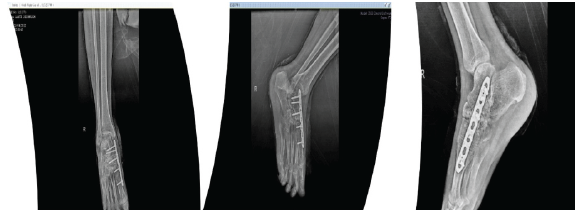

After the diagnosis of GCT was established, the patient was prepared for excision of the lesion using curettage and chemical cauterization. To impart more stable fixation and to fill the void of excision, bone grafting along with plate (3.5 mm combihole plate) fixation was done (Fig. 6, 7).

Figure 6: Intraoperative images.

Figure 7: Immediate post-operative X-rays.

Neo adjuvant denosumab therapy was given pre and intraoperatively and at regular intervals. (denosumab 120 mg on day 0, 8, 15, 28) [5].

Denosumab leads to downsizing of the tumor and leads to fibrosis of the margin and inhibiting progress of the disease [4,5]; hence, a planned resection may become less morbid when preoperative denosumab is administered [6]. There is no confirmation of improved local control post-surgery, but more importantly, no increase in recurrence rates has been confirmed either [7]. En-bloc resection of GCTB, especially in the case of soft-tissue involvement, can be facilitated by a neoadjuvant denosumab regimen. The optimal treatment duration and maintenance dose and interval of denosumab in unresectable disease are still under analysis [8,9]. After stopping denosumab, the incidence was increased which was noted in few studies [10] (Fig. 8, 9).

Figure 8: 8-month follow-up X-rays.